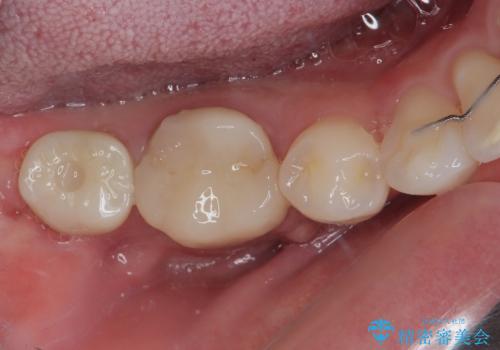

埋伏している右下第二大臼歯は、牽引して咬合に参加させることで計画しましたが、癒着などにより移動困難な場合には、抜歯の上インプラント補綴治療を行うこととしました。

右下の埋伏歯はやはり癒着しており、抜歯の後にインプラントを埋入することとなりました。

埋伏歯の牽引や、奥歯の咬み合わせ改善、インプラント補綴治療と治療期間が延びてしまう要素が多く、治療は難航しましたが、最終的に非常に満足のいく仕上がりとなりました。